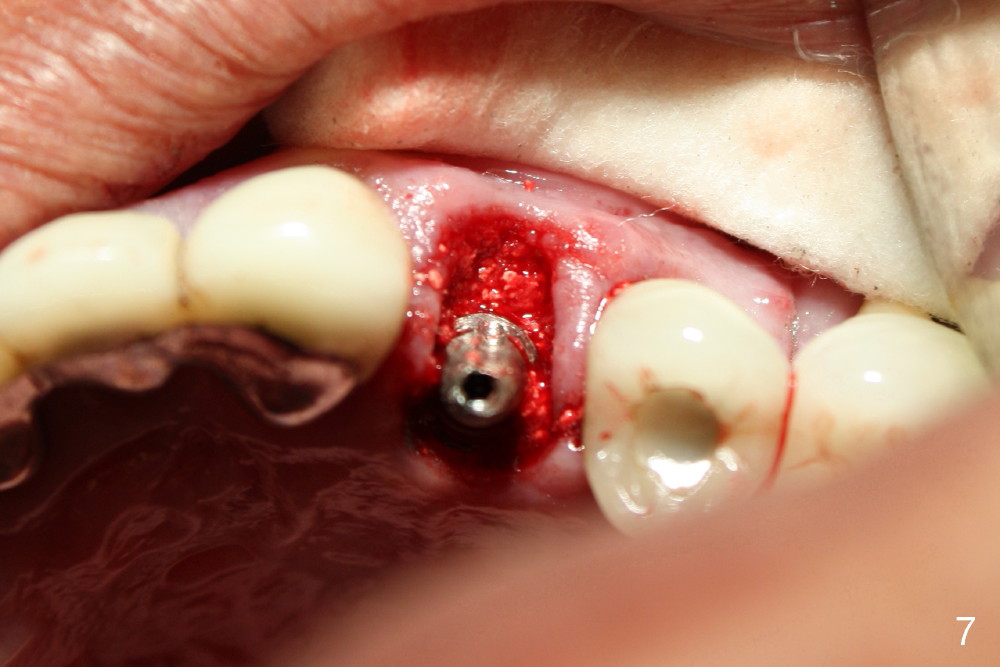

A 50-year-old man has mild pain in the upper left 1st bicuspid 3 years after root canal retreatment with placement of two posts (Fig.1). Findings of clinical exam are consistent with root fracture (Fig.2). Extraction reveals two fused roots (Fig.3,4). Probing indicates that the buccal plate is defective. Osteotomy is initiated in the palatal socket with a 2 mm pilot drill, followed by 2.5 and 3.0 mm reamers and 4.5x20 mm tap. The septum appears to have been pushed buccally (Fig.5 *) and form a new buccal wall (partially, strengthened by bone graft mentioned below) for the implant to be placed. The implant (4.5x20 mm) is placed in the palatal socket (Fig.6 *) with insertion of an abutment (A: 3.5x5 mm 0º), while a mixture of autogenous bone (harvested from reamers) and Synthograft (Bicon) is placed in the shrunken buccal socket (Fig.7; using allograft may decrease postop bony shrinkage). The bone graft is then contained by an immediate provisonal without collagen membrane or flaps. The patient is doing well postop. The gingiva is healthy (Fig.8*) when the provisional is removed 3 months postop with normal papillae (Fig.9 arrowheads). It remains the same 1 month post cementation (Fig.10,11). For further follow up, see immediate implant of the tooth #13.